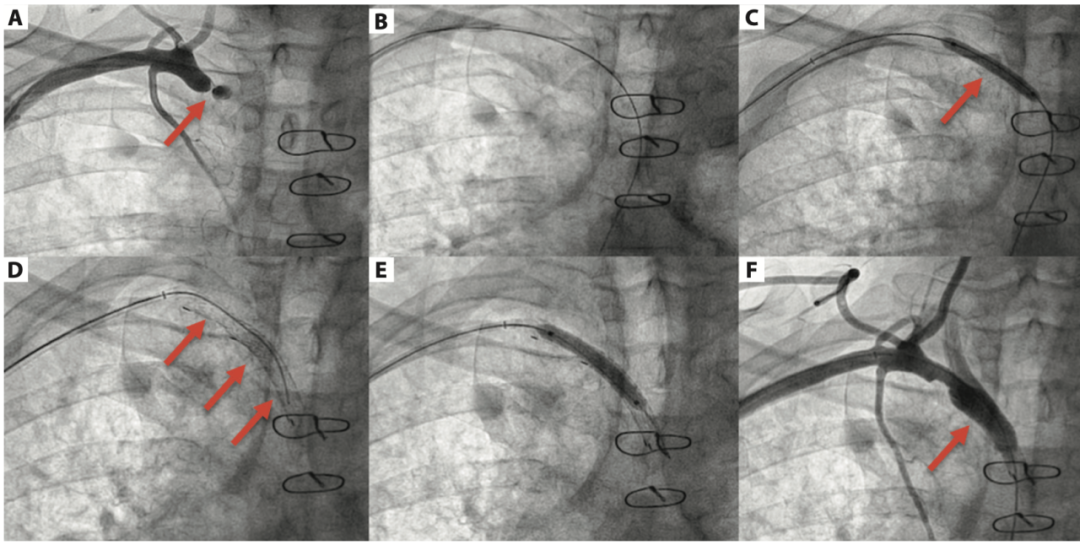

文献报道

双侧桡动脉入路和冠脉术中处理锁骨下狭窄

Tao, Qiu,Sheng-Qi, Fu,Xiao-Yong, Deng et al. Subclavian artery stenting via bilateral radial artery access: Four case reports.[J] .World J Clin Cases, 2022, 10: 0.

Ahmed Mahmoud, El Amrawy,Santiago, Camacho-Freire,Antonio, Gomez-Menchero et al. Subclavian angioplasty during coronary interventions using radial approach.[J] .Kardiol Pol, 2022, 80: 0.